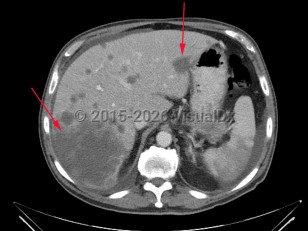

Liver cancer refers to a malignancy that arises primarily within the liver. There are several types of liver cancers. Hepatocellular carcinoma, accounting for approximately 75% of primary liver cancers, is due to malignant transformation in hepatocytes. This is most commonly seen in patients with cirrhosis of any etiology (eg, chronic viral hepatitis, alcohol-related liver disease, nonalcoholic steatohepatitis). Cholangiocarcinoma is the second most common primary liver cancer, accounting for approximately 10%-20% of cases. This is a cancer of bile duct origin.